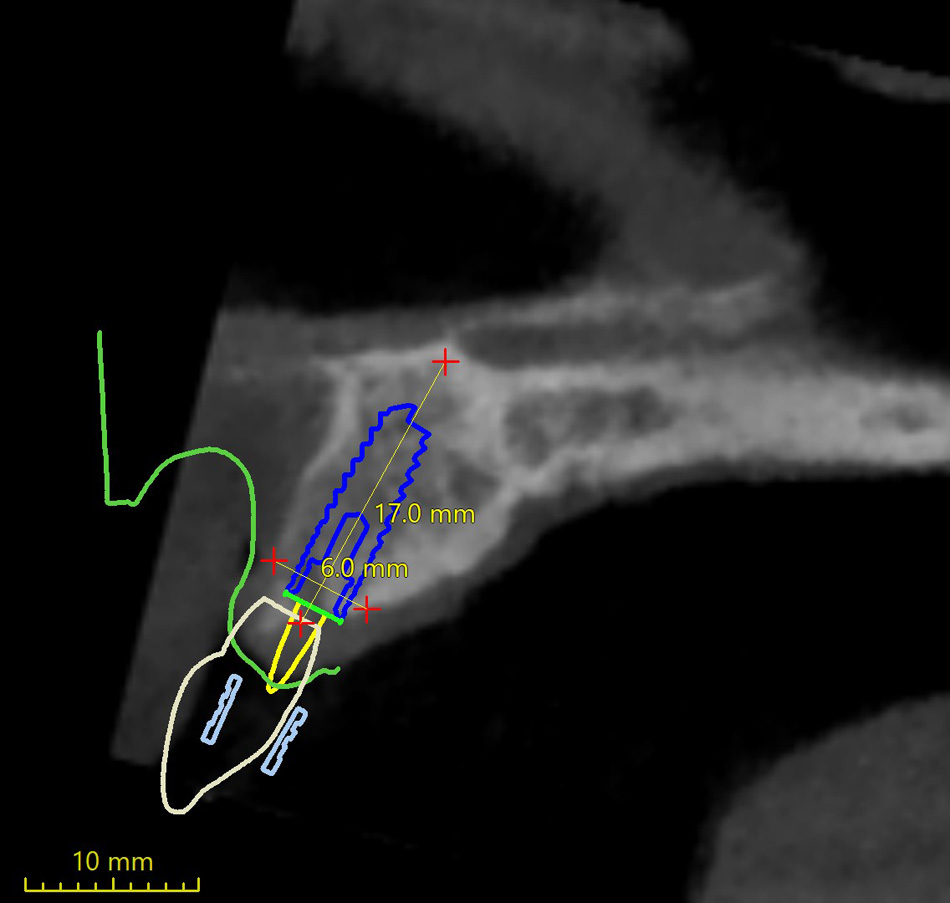

Lékař si vytvoří všechny typy zobrazení potřebných pro naplánování – tedy 2D snímky (panoramatický), příčné řezy i 3D model.

Vidí zde i důležité anatomické útvary – čelistní dutinu, průběh nervu atd. Po proměření množství kosti – šířky i výšky vybere z databáze vhodný typ implantátu a umístí ho do požadované lokality. Ihned vidí jeho pozici ve všech 3 rovinách a na všech snímcích i 3D modelu. Může upravovat podle potřeby jeho pozici, sklon atd.

Všechny vybrané a správně umístěné simulované implantáty se ukládají do „počítačové karty“ pacienta s jejich pozicí, délkou, průměrem, typem i sklonem. V programu také lékař navrhuje chirurgické šablony pro řízenou nebo navigovanou implantaci. Lékař i pacient tedy ještě před vlastní operací vidí, jak by mělo ošetření probíhat a vypadat.

4) Naplánování pozic, délek a průměrů implantátů

5) Naplánování virtuálního markeru pro navigaci